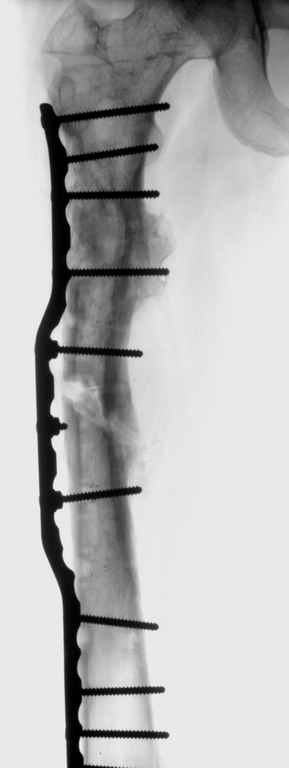

Возможна аппаратная коррекция оси с формированием клиновидного регенерата, которая решила бы и проблему укорочения (что, впрочем, нужно уточнить по схеме, сделанной по рентгенограмме с хорошим захватом смежных суставов - схемка по присланному снимку в приложении). По окончании коррекции - блокируемый стержень, который и сократит время пребывания в аппарате, и вообще возврата к нормальной жизни, а также будет мерой профилактики патологических переломов.

Alexander Chelnokov 15 Ноябрь 2004, 17:55

По имеющемуся снимку и по первоначальной информации - ничего плохого про сустав не было, почему думать сейчас о протезе? Касательно бедра - можно подумать и про "отколенное" введение интрамедуллярного гвоздя,

возможно, не с одной остеотомией, а с двумя, если будет тенденция к перфорации стенки канала из-за кривизны.

Собственно сустав не беспокоит, объем движений полный. По скиаграммам получается, что достаточно одной остеотомии на вершине деформации, чтобы восстановить длину и вывести коленный сустав в нужное положение.

Т.к. укорочение 7 см, то начинать будем с соеотомии и коррекции аппаратом. Спасибо

Моё мнение, что двойная остеотомия бедра с аппаратом Илизарова + Гексаподный механизм, или Тэйлора, В данной ситуации является методом выбора. Я очень извеняюсь за качество прилагаемых снимков, в которых я постарался отразить разницу междe одной и двумя остеотомиями бедра.

jo> отразить разницу межде одной и двумя остеотомиями бедра.

Скорее всего, второй уровень может оказаться нелишним лишь при переходе с аппарата на интрамедуллярный стержень. И его не поздно будет пересечь именно в момент введения гвоздя, если будет угроза перфорации стенки канала.